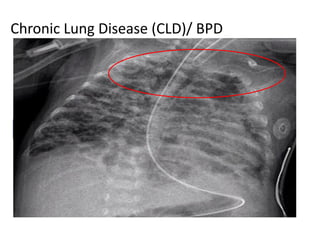

Chronic Lung Disease (CLD)/ BPD

Chronic Lung Disease(CLD)/ BPD Fetal Lung Development Postnatal Lung Growth And Development Pulmonary Outcome Initiation Of Breathing Mechanical Ventilation Oxygen Infection Preterm Labour Preterm Delivery CANNALICULAR STAGE SACCULAR STAGE ALVEOLAR STAGE